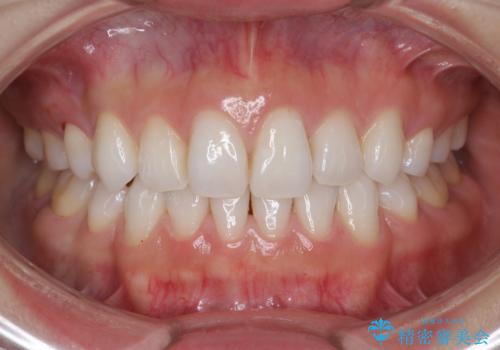

食いしばりが強い方はセラミックがまた割れる可能性があるため、予防的にナイトガードを装着することをお勧めします。

- かみ合わせや歯ぎしりが強すぎる方はセラミックが割れてしまう可能性があります